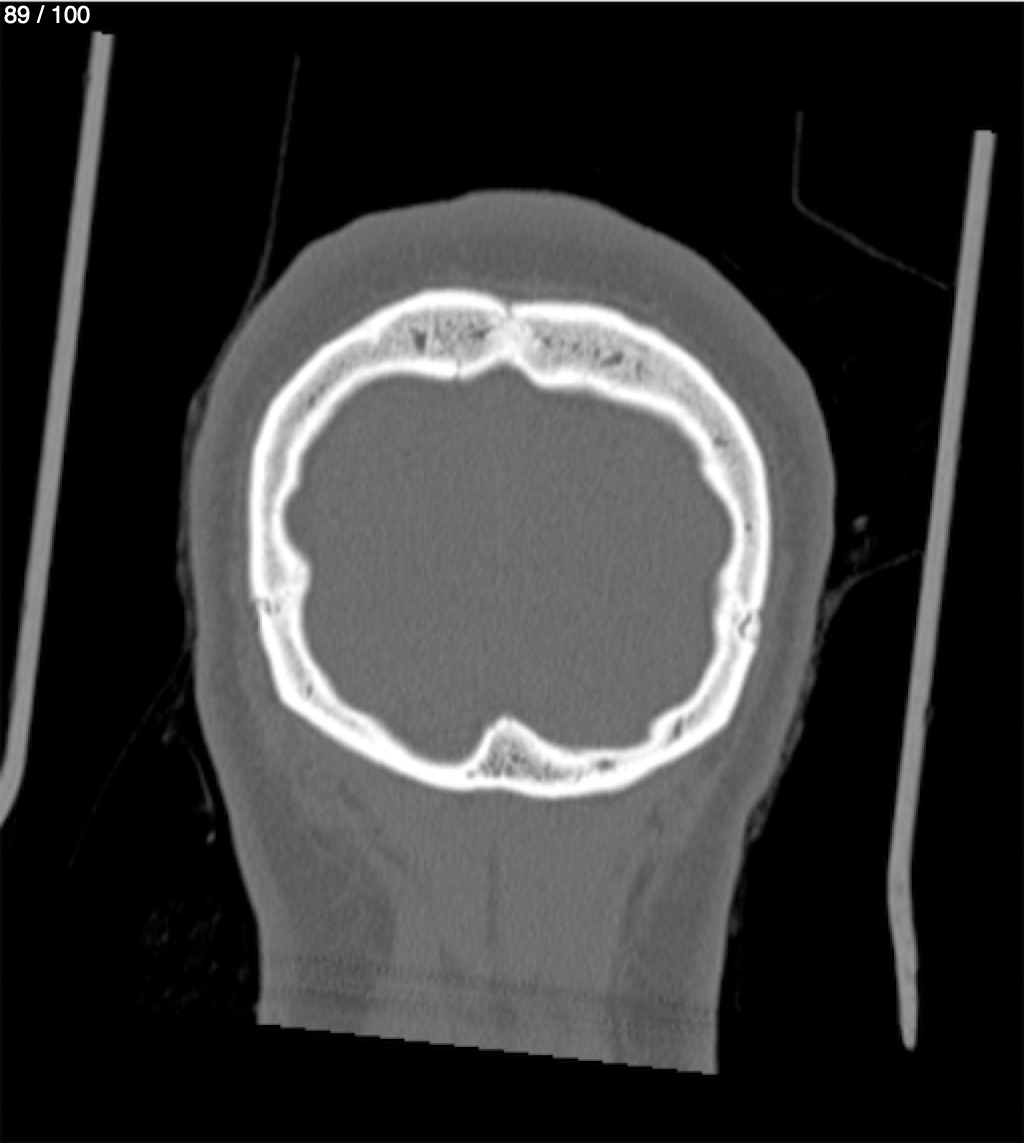

Reybet Garcia Fuentes 30A - T.C Craneo